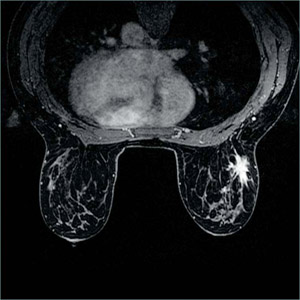

図8 VIBBRANT-FLEXの画像例

浸潤性小葉癌のVIBRANT-FLEXによる造影後アキシャル像。

心臓からのアーチファクトも非常に少ない。

(画像ご提供:聖隷浜松病院様)